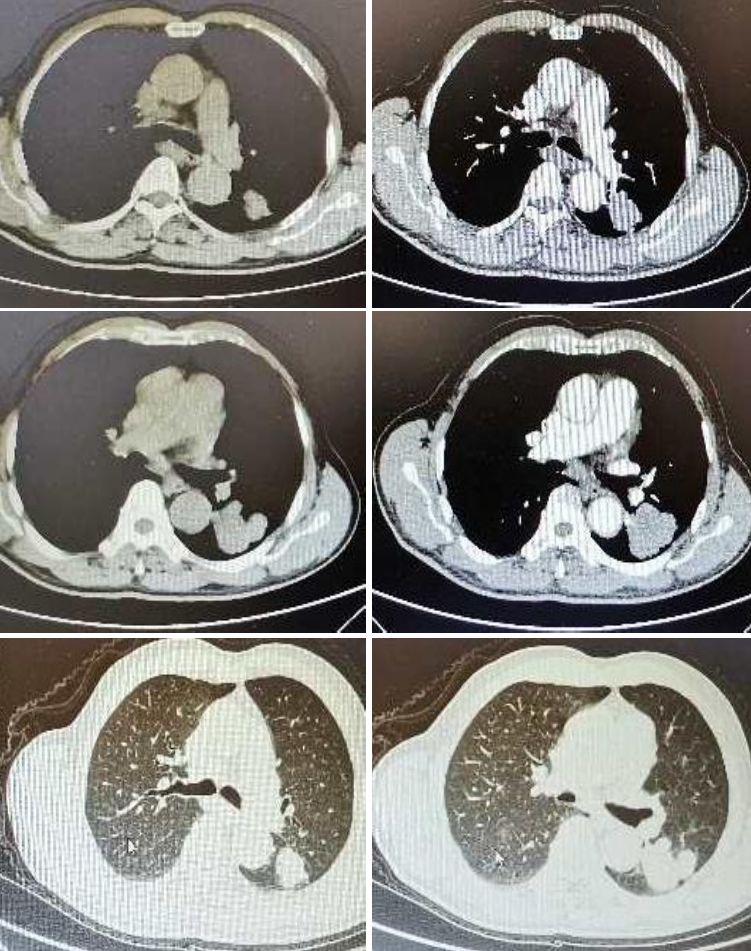

诊断:肺癌脑转移。患者老年男性,影像特征是小病灶大水肿,考虑转移瘤。补充患者胸部CT如下: